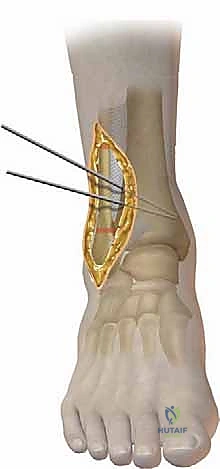

| قطع العظم الإسفيني المفتوح (Opening Wedge Osteotomy) | يتم عمل شق في العظم وفتحه لإضافة زاوية، ثم يُملأ الفراغ بطعم عظمي (Bone Graft) صناعي أو من المريض. | يطيل العظم (مفيد إذا كان هناك قصر في الساق)، دقيق جداً في التصحيح. | يحتاج إلى طعم عظمي، قد يستغرق وقتاً أطول للالتئام. |

- قص العظم (Osteotomy): باستخدام منشار جراحي دقيق وموجهات خاصة، يتم قص عظم الظنبوب (وفي بعض الأحيان عظم الشظية أيضاً) بالزاوية التي تم تحديدها مسبقاً في التخطيط الثلاثي الأبعاد.

- تصحيح المحور: يتم فتح أو إغلاق الشق العظمي للوصول إلى المحور الميكانيكي السليم للكاحل. يتم التحقق من ذلك داخل غرفة العمليات باستخدام جهاز الأشعة السينية الفلوروسكوبي (C-arm).

- التثبيت الداخلي (Internal Fixation): بمجرد الوصول للزاوية المثالية، يتم تثبيت العظم في وضعه الجديد بقوة باستخدام شرائح معدنية متطورة (Locking Plates) ومسامير من التيتانيوم. هذا التثبيت القوي يضمن عدم تحرك العظم أثناء فترة الالتئام.